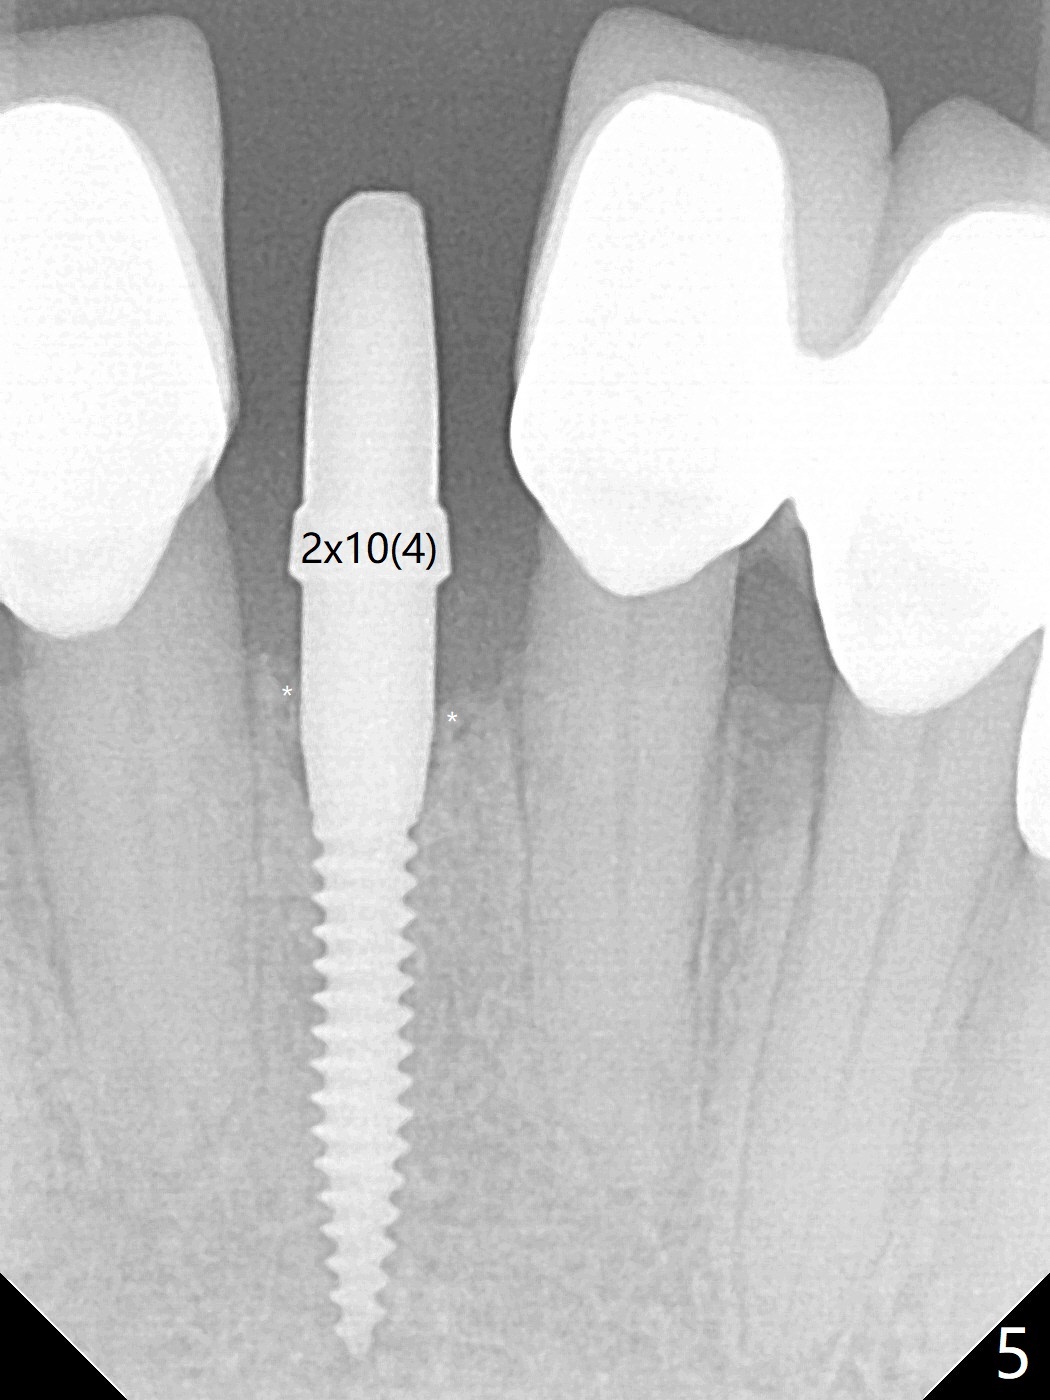

种植前与66岁女病人再次讨论下前牙正中种植可能产生不对称问题,她好像不在乎。术前检查显示下前牙正中间隙偏左(图一),处理似乎容易,但是牙槽嵴相当狭窄(图一 *,二 箭头)。牙槽嵴切除后(大约3 毫米宽(颊舌侧)),初期钻洞似乎偏移右边(图三),矫正后(图四),植入2乘10(4)毫米连体植体(图五,比预计小,因为骨质薄),放置骨粉(图五,六 *)和膜,缝合,制作即刻修复物(图七 T),病人满意,牙槽骨饱满了。术后一个多月临时牙冠取出修正,伤口愈合,由于植骨颊侧没有凹陷(图八),而舌侧隆起(图九:*,与图二术前对比)。其实病人不小心吃牛肉时损伤植体,疼痛几天。尽管最近吃饭时植牙又受伤,但是没有松动,也没有骨质吸收,就是局部结石多(图十,术后四个月)。正式牙冠术后4.5个月粘固(图十一)。